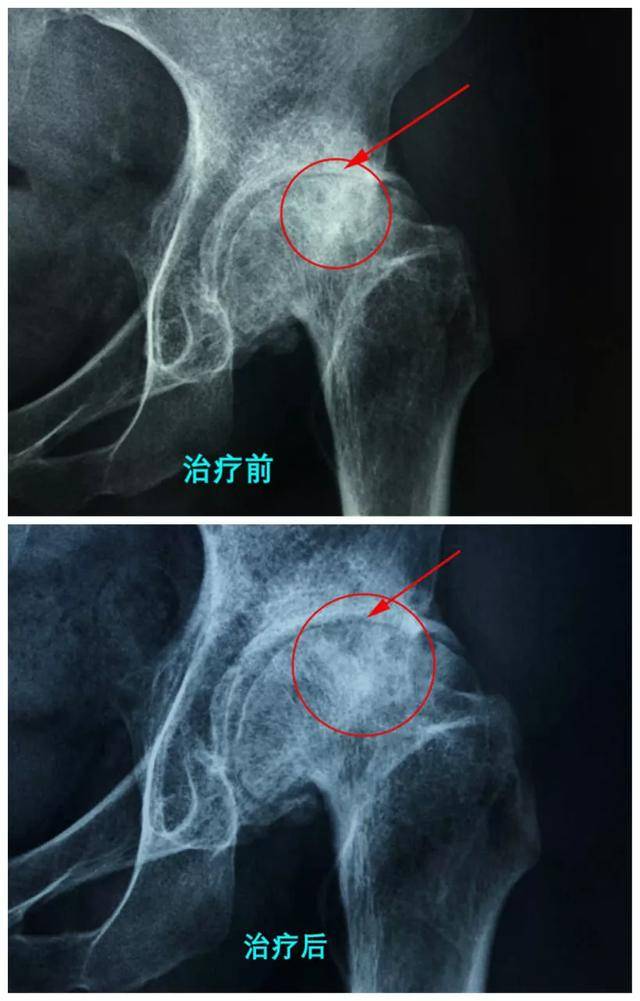

在衡水股骨头医院,我们注重为患者提供科学严谨的保守治疗,以帮助他们应对股骨头坏死。通过详细的临床评估,我们会制定个性化的治疗计划,结合物理治疗、药物管理及康复训练,力求为每位患者减轻疼痛、提高生活质量。这种方法不仅能够有效减缓疾病进展,还能帮助患者在日常生活中恢复更好的运动能力。医院拥有经验丰富的医生团队,全程跟踪病情进展,及时调整治疗方案,确保达到最佳效果。相信通过这些科学而系统的措施,可以有效避免不必要的置换手术,让患者重返健康轨道。

在对股骨头坏死的保守治疗中,近年来出现了一些新技术,能够有效帮助患者减轻疼痛,并避免进行置换手术。首先,超声波引导下的干针疗法,通过准确定位可以直接作用于关键病灶,促进局部血液循环,缓解疼痛和炎症。此外,关节内注射治疗,尤其是透明质酸和类固醇注射,能够在一定程度上减轻关节疼痛,提高运动功能。更重要的是,多种物理疗法结合使用,如电刺激和理疗,可以进一步改善患者的康复效果。这些新技术不仅提升了患者的生活质量,也为股骨头坏死提供了非手术性解决方案,使得许多患者能够恢复正常运动能力。